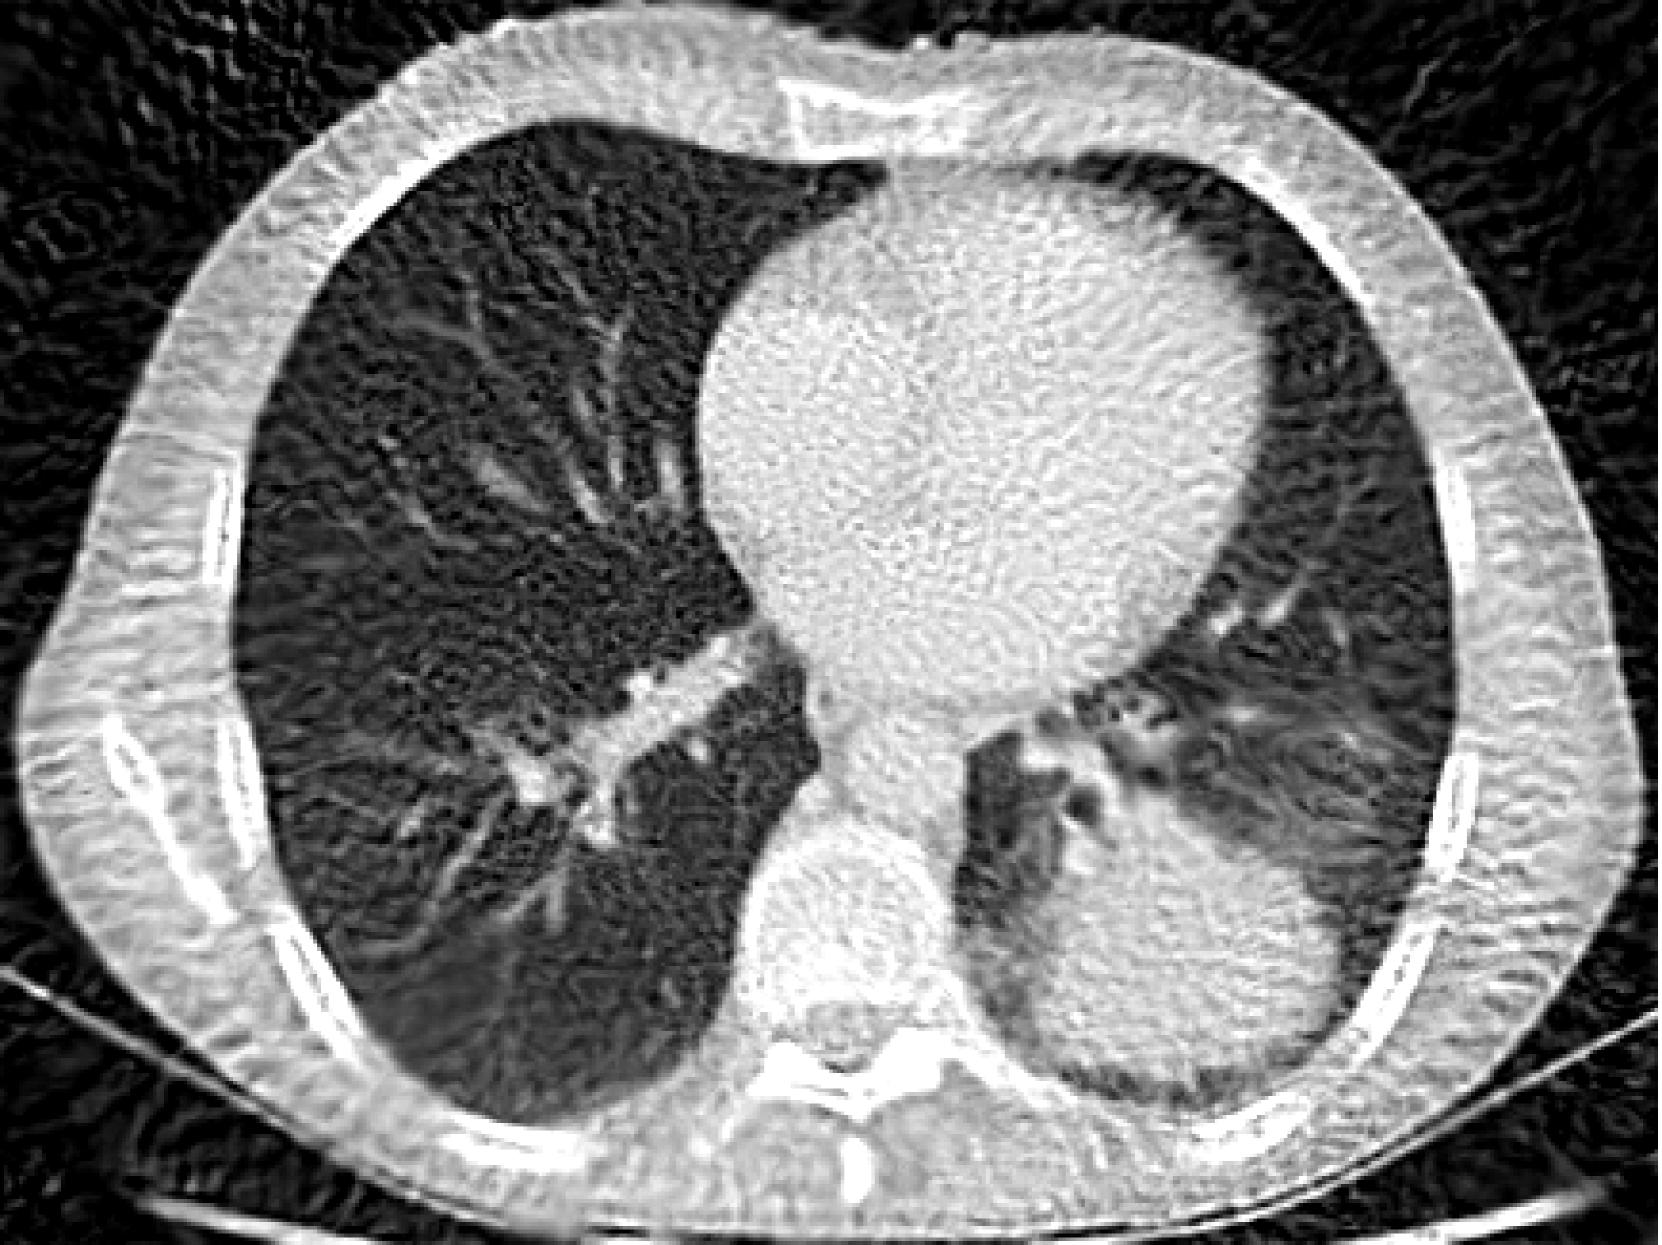

5.4 Low Norm Solutions and Inverse Problems

For our last experiment we trained the BW-ReLU neural network for the CT reconstruction task with three different scaling parameters. In Figure 7 all three BW-ReLU neural networks that were used to reconstruct the image achieved the same training loss on the CT measurement data. However we see that the model with the smallest variation norm across all 3 layers corresponds to the best reconstruction. This suggests a principled methodology for choosing the scaling parameter c𝑐citalic_c in the case of inverse problems.

g𝜽𝒱=8650subscriptsubscriptnormsubscriptsuperscript𝑔𝜽𝒱8650\sum_{\ell}\|g^{\ell}_{\bm{\theta}}\|_{\mathcal{V}}=8650∑ start_POSTSUBSCRIPT roman_ℓ end_POSTSUBSCRIPT ∥ italic_g start_POSTSUPERSCRIPT roman_ℓ end_POSTSUPERSCRIPT start_POSTSUBSCRIPT bold_italic_θ end_POSTSUBSCRIPT ∥ start_POSTSUBSCRIPT caligraphic_V end_POSTSUBSCRIPT = 8650

(a) PSNR: 29.9 dB

c=1𝑐1c=1italic_c = 1

g𝜽𝒱=1978subscriptsubscriptnormsubscriptsuperscript𝑔𝜽𝒱1978\sum_{\ell}\|g^{\ell}_{\bm{\theta}}\|_{\mathcal{V}}=1978∑ start_POSTSUBSCRIPT roman_ℓ end_POSTSUBSCRIPT ∥ italic_g start_POSTSUPERSCRIPT roman_ℓ end_POSTSUPERSCRIPT start_POSTSUBSCRIPT bold_italic_θ end_POSTSUBSCRIPT ∥ start_POSTSUBSCRIPT caligraphic_V end_POSTSUBSCRIPT = 1978

(b) PSNR: 28.7 dB

c=2𝑐2c=2italic_c = 2

g𝜽𝒱=1292subscriptsubscriptnormsubscriptsuperscript𝑔𝜽𝒱1292\sum_{\ell}\|g^{\ell}_{\bm{\theta}}\|_{\mathcal{V}}=1292∑ start_POSTSUBSCRIPT roman_ℓ end_POSTSUBSCRIPT ∥ italic_g start_POSTSUPERSCRIPT roman_ℓ end_POSTSUPERSCRIPT start_POSTSUBSCRIPT bold_italic_θ end_POSTSUBSCRIPT ∥ start_POSTSUBSCRIPT caligraphic_V end_POSTSUBSCRIPT = 1292

(c) PSNR: 32.1 dB

c=3𝑐3c=3italic_c = 3

g𝜽𝒱=1571subscriptsubscriptnormsubscriptsuperscript𝑔𝜽𝒱1571\sum_{\ell}\|g^{\ell}_{\bm{\theta}}\|_{\mathcal{V}}=1571∑ start_POSTSUBSCRIPT roman_ℓ end_POSTSUBSCRIPT ∥ italic_g start_POSTSUPERSCRIPT roman_ℓ end_POSTSUPERSCRIPT start_POSTSUBSCRIPT bold_italic_θ end_POSTSUBSCRIPT ∥ start_POSTSUBSCRIPT caligraphic_V end_POSTSUBSCRIPT = 1571

(d) PSNR: 29.1 dB

c=5𝑐5c=5italic_c = 5

Figure 7: Four BW-ReLU DNNs trained on the CT reconstruction task with different values of c𝑐citalic_c. All networks are trained to the same training loss. We see that the c𝑐citalic_c which produces the highest PSNR corresponds to the one with the lowest variation norm across all layers.